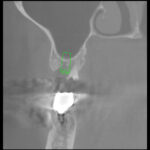

ソーセージテクニックは難しいといわれている垂直的に骨造成をするテクニック。先端美容テクニックといえます。3DX画像

まずは予防プログラムに入って磨き方のコーチングをさせていただきました。優秀で優しい衛生士です。見る見るうちに綺麗に磨けるようになりました。抜歯もかなり困難でした。骨に癒着していました。抜歯後上顎洞までの距離はわずか1㎜。まずは抜歯の穴が吸収しないための骨再生療法。抜歯後8週間でさせていただきました。それから4カ月まちました。CT診断で、サイナスリフトはしなくてすみます。更に骨を増やすためにソーセージテクニックをおこないました。インプラントごと骨の不足した部分に骨材を足します。そして、骨材料を吸収性のメンブレンで包みます。タックで留めます。十分な量の骨量を確保できそうです。